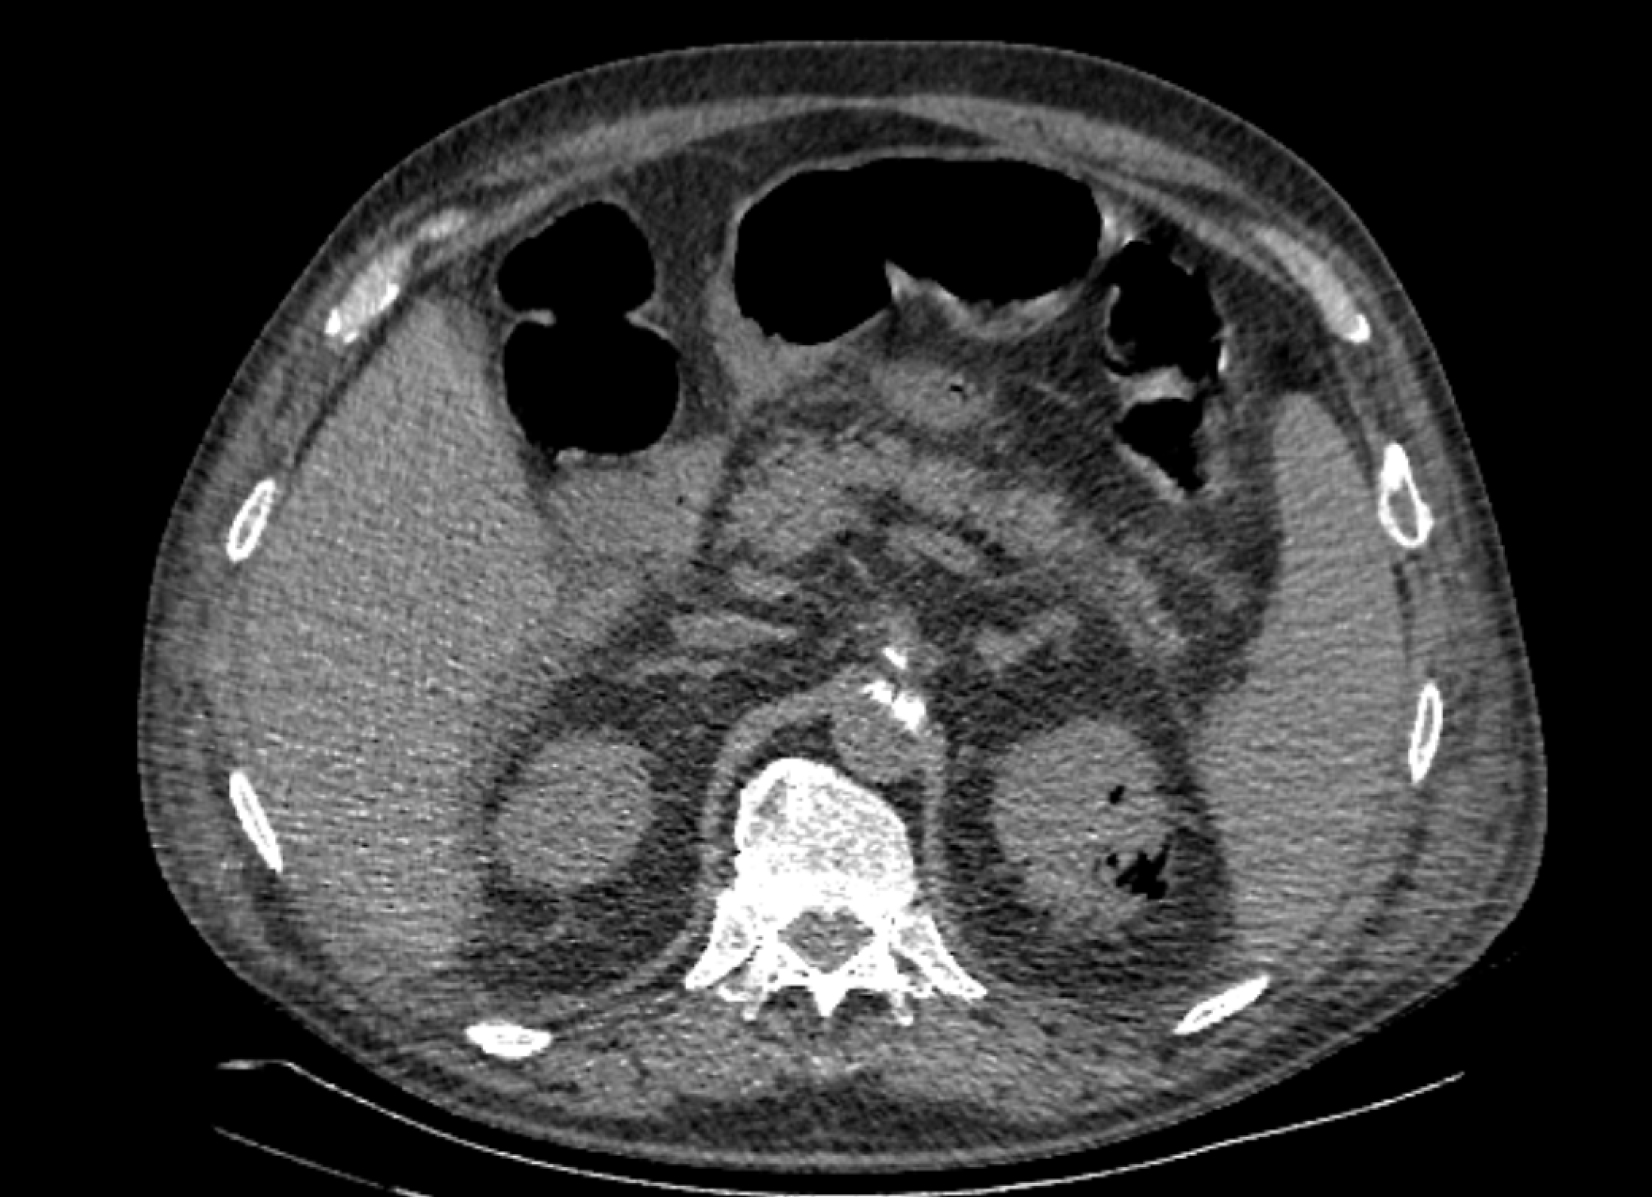

На следующий день состояние пациента оставалось тяжелым, с отрицательной динамикой, креатинин сыворотки возрос до 735,2 ммоль/л, Появились жалобы на слабость, тошноту. При осмотре: живот мягкий, вздут по всем отделам, при пальпации болезненный. Область почек не изменена, при пальпации безболезненна, патологических изменений в области почек не выявлено. Симптом поколачивания отрицательный билатерально. При УЗИ были обнаружены плевральный выпот по 300–400 мл с каждой стороны, гепатомегалия, увеличение размеров селезенки, асцит. Кроме того, в обеих почках были визуализированы тени, характерные для конкрементов. По данным компьютерной томографии (КТ) конкрементов не обнаружено, но в лоханке, на всем протяжении левого мочеточника и, частично, в правом мочеточнике, а также в мочевом пузыре визуализировался газ (рис. 1–6).

Рис. 4. Компьютерная томография органов брюшной полости, забрюшинного пространства, органов малого таза. Газ в почках

Рис. 5. Компьютерная томография органов брюшной полости, забрюшинного пространства, органов малого таза. Газ в левой почке